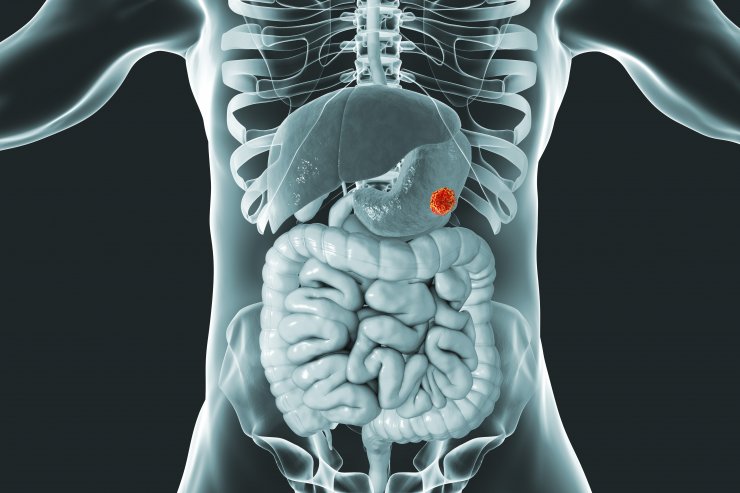

Krebserkrankungen des Magen-Darm-Traktes sind weltweit für 26% der Krebserkrankungen und 35% aller krebsbedingten Todesfälle verantwortlich. Allein im Jahr 2018 wurden weltweit etwa 4,8 Mio. neue gastrointestinale Krebsfälle und 3,4 Mio. damit verbundene Todesfälle erfasst.